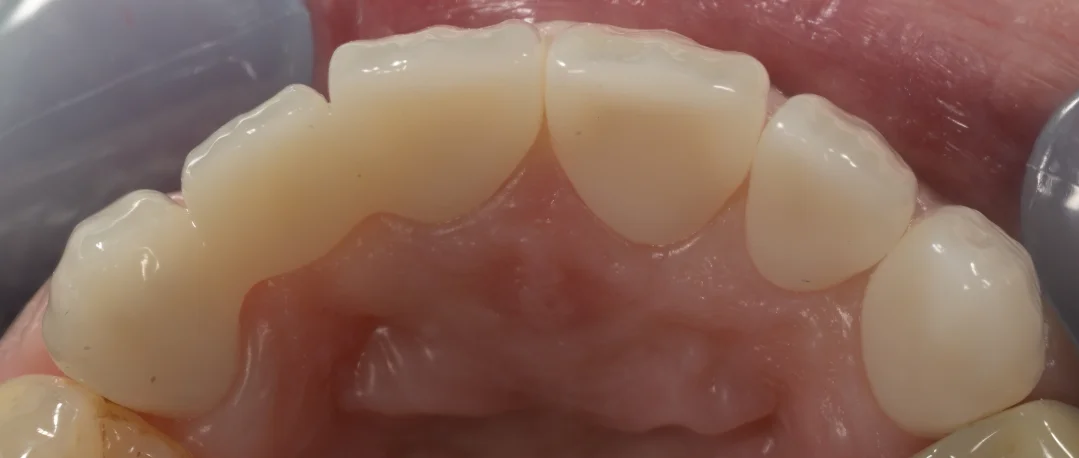

噛む面から撮影したものがこちらになります。

元々保険ブリッジの入っていた右上の歯の状態がやはり悪く、深いところまで虫歯になっていたため、型取りが非常に大変でした・・・。

画面いちばん左の歯の内部に黒いのが見えていますが、これは前回の治療の時に使用していた土台部分の金属の色が沈着した部分ですので、虫歯ではありません。

むしろここを除去すると歯が折れるリスクが高くなるため、今回は温存しました。

プロビジョナルの時点で歯ブラシを相当頑張ってくれていたので、これだけ歯茎の深くまで削り込んだケースでも、歯茎に炎症がほぼなく綺麗な状態でした。